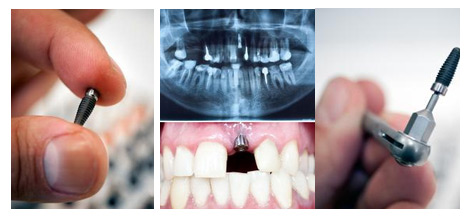

西安雁塔海涛口腔医院医生介绍说,单颗牙齿缺失优选种植牙修复,种植牙类似真牙原理,以手术方法在口腔牙槽骨组织中植入人工牙根(种植体)作为支持,并在人工牙根上进行牙冠修复的一种缺牙修复方法。因为种植牙可以获得与天然牙功能、结构以及美观度一样的修复效果。

【医生指导】目前更好的修复方法就是种植牙了,有自己的人工牙根,外形上与自己的牙是一样的,维护得当,可以用一辈子。